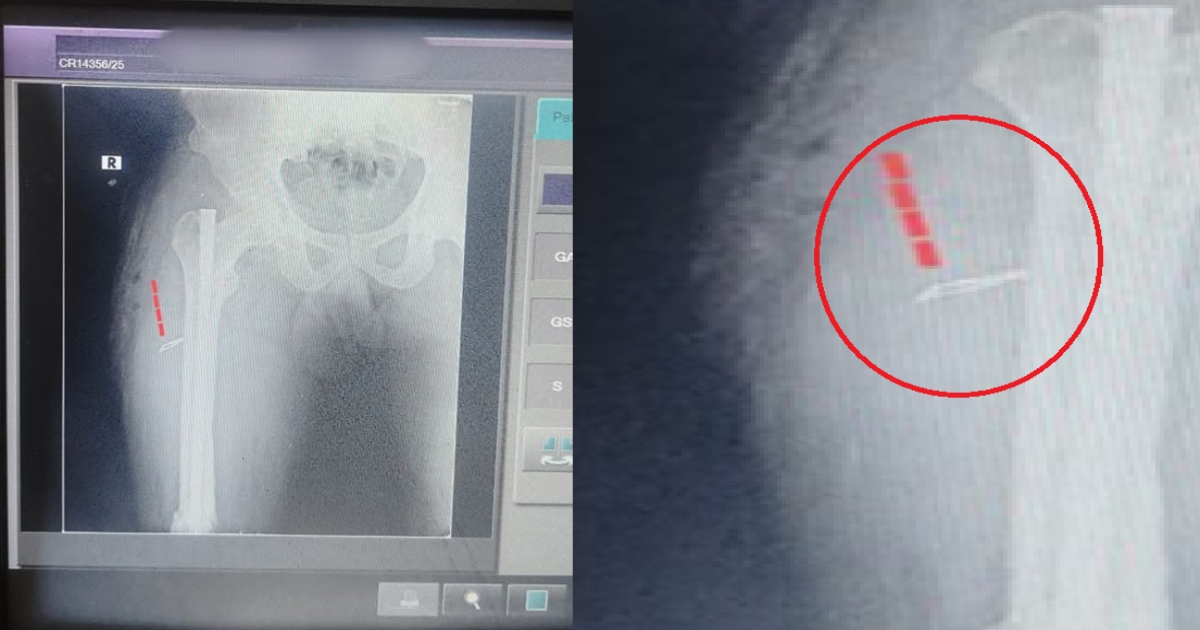

விபத்தில் காயமடைந்தவருக்கு காலில் சிசேரியன் பிளேடு வைத்து தைத்து மருத்துவர்கள் அனுப்பி உள்ளனர். ஒரு வருடத்துக்கு பின் போல்டை அகற்ற சென்றவருக்கு இந்த அதிர்ச்சி சம்பவம் தெரிய வந்துள்ளது.

அங்கு அவரை பரிசோதித்த மருத்துவர்கள் அறுவை சிகிச்சை செய்ய அறிவுறுத்தியுள்ளனர். இதனால் அறுவை சிகிச்சை செய்யப்பட்ட நிலையில், அவரது கால் வலி மோசமாகி இருக்கிறது. உள்ளே ஒரு கம்பி வைக்கப்பட்டு அறுவை சிகிச்சை செய்யப்பட்டதாக தெரியவரும் நிலையில், ஒன்றரை ஆண்டுகளுக்கு பின்னர் வெளிப்புற போல்டை அகற்றினால் அது சரியாகிவிடும் என மருத்துவர்கள் தெரிவித்துள்ளனர்.

பின் வீட்டிற்கு திரும்பிய சின்னா நாளுக்கு நாள் கால் வலியால் அவதிபட்டுள்ளார். இதனால் மீண்டும் மருத்துவமனைக்கு சென்று போல்ட்டை அகற்ற கேட்டபோது அவரது கால் உள்ளே சிசேரியன் பிளேடு வைத்து தையல் போடப்பட்டது தெரிய வந்துள்ளது. இதனை தொடர்ந்து உடனடியாக மருத்துவர்கள் காலில் இருந்த சிசேரியன் பிளேடை அறுவை சிகிச்சை செய்து அகற்றினர்.